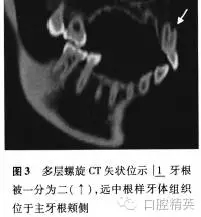

根尖X線片示:|1牙根被縱向線狀投射影分為近中和遠(yuǎn)中兩個牙根,遠(yuǎn)中牙根根尖牙周膜增寬,疑似根折或雙牙根。為進一步明確診斷,行多層螺旋CT(Somatom Sensation 16,西門子,德國)檢察,CT影像示:牙根唇面及舌面溝樣凹陷自牙頸部向根尖部逐漸加深,至根中1/3兩者貫通將牙根一分為二,遠(yuǎn)頰“額外根”內(nèi)未見低密度影像,提示“額外根”內(nèi)無牙髓組織,為實心牙體組織,“額外根”周圍可見低密度影像(圖1-3)。

多層螺旋CT顯示該牙根被兩個向根尖部逐漸加深的唇面溝和舌面溝在根中1/3分開,在主根管遠(yuǎn)頰側(cè)形成“額外根”,CT冠狀位、矢狀位及軸位影像顯示“額外根”中未見低密度影像深入,提示此“額外根”內(nèi)無牙髓組織,因此可以排除雙根管,確診是由于畸形根面溝造成的額外牙體組織突起。